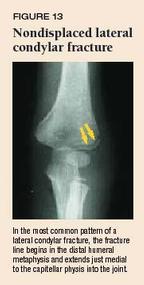

Specific fractures . A number of fractures have been recognised as highly specific to non-accidental injuries (rather than accidental injury) . They include: metaphyseal fracture (so-called bucket handle fracture or corner fracture ) present in up to 39-50% of abused infants <18 months; said to be virtually pathognomonic of NAI; rib fractures